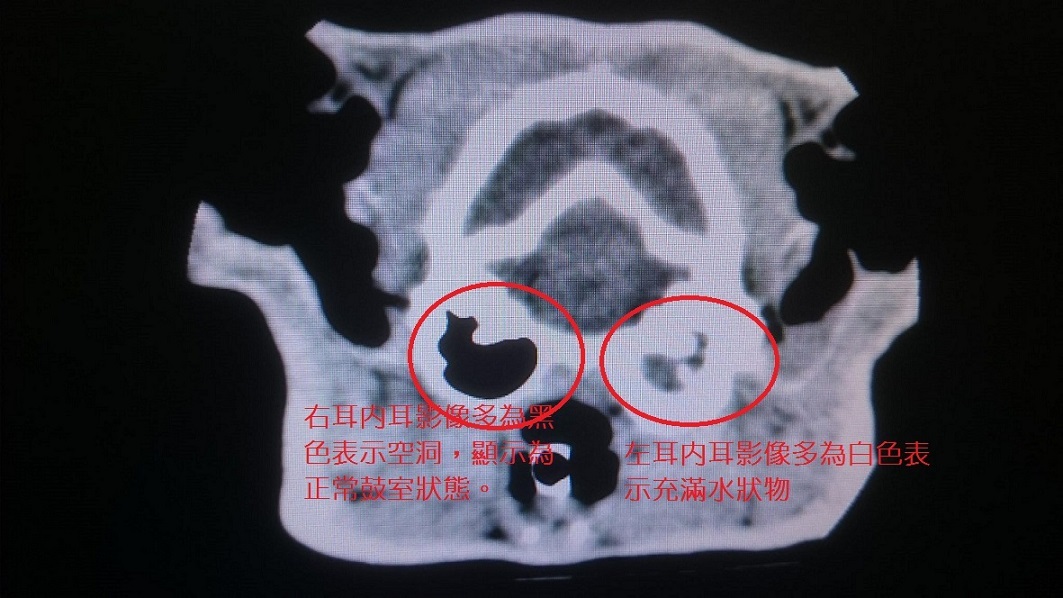

丁丁於2/23進行內耳膿水清除及耳道腫瘤夾除的手術,術前醫生不斷告知此手術後喵會非常疼痛,術前並在側腹貼上瑪非貼片。

這次手術是從左側下巴下面開洞將內耳裡的膿水清除乾淨,並把耳道的腫瘤一併夾除,手術進行近4個小時,術後因麻藥漸退及疼痛的關係,丁丁不斷大發飆,為了不讓他在醫院的籠內撞來撞去,我只好一直抱著他,但他不斷發狂一個人實在控制不住,我嘴脣被他抓破2個洞,衣服也被抓破且都是血,看他這樣疼痛實在讓人不忍心...幸好回家後可能醫生再給的瑪非止痛藥發揮作用,丁丁情況穩定許多,且有點稍HIGH的狀況,反而不斷在他的籠子裡面滾來滾去類似嗑喵草的樣子也不斷的呼嚕嚕。

手術後連幾天醫生都每天電話詢問丁丁狀況,非常感謝醫生的細心,術後裝在脖子處的引流管也需每天換紗布,流出的分泌物也有慢慢減少的情況,1周後於3/3再次回診,醫生告知狀況都很不錯,這1周也明顯不再從左耳甩出液體了。

醫生告知此次手術送驗的膿水和腫瘤確實有很多細菌反應,後續需每周回診打長效抗生素至少4~8周來幫助控制內耳的發炎情況,之後需再一併觀察,若復元狀況良好有機會不需再次做任何耳道摘除等的侵略性手術。

此次手術及術前血檢費用共30000元懇請大家多多幫忙丁丁,剩餘的病理切片及細菌培養等費用4250元由志工自行支付,再請大家多多幫忙丁丁的手術費用!!!!大感謝!!!動物近況說明: 最近一次3/10回診,血檢狀況良好,施打第4次長效抗生素,左耳用耳鏡進去看的結果也很好,裡面已呈現乾燥如健康耳朵,眼睛的反射也正常,雖左眼第3眼瞼仍未收回,醫生告知因那部分的神經就在內耳,有可能手術過程造成破壞,之後可能有機會慢慢恢復,端視手術時對神經的破壞程度,目前無法評估完全恢復需多久時間,但對丁丁生活及視力無太大影響,他目前狀況都很好,未來再看他的情況也許會嘗試送養。